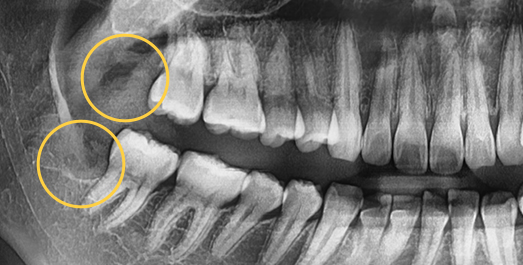

• Horizontally

impacted wisdom tooth

• Angulated

• Vertically